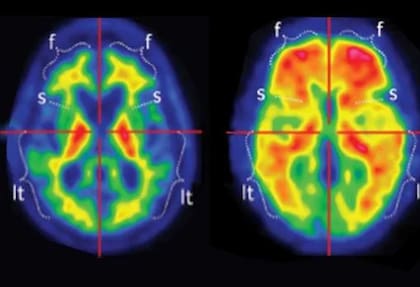

Las enfermedades neurológicas abarcan un espectro amplio y complejo. Los neurólogos tratan desde accidentes cerebrovasculares y trastornos convulsivos hasta enfermedades neurodegenerativas, problemas del movimiento, alteraciones musculares, cefaleas y trastornos del sueño.

Esta diversidad hace que muchos síntomas se confundan con molestias pasajeras o propias de la edad, lo que retrasa diagnósticos clave.